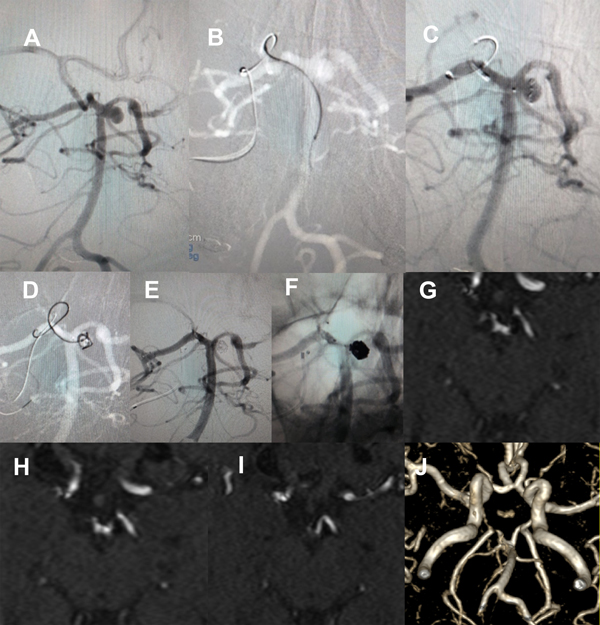

En nuestra serie, el resultado inmediato ideal se obtuvo en 8 de 19 pacientes (42%), con 9 remanentes de cuello, y remanente de saco en 1 caso que fue retratado y en control posterior volvió a mostrar permeabilidad (figuras 2-4).

Fig. 2. Paciente 1, caso 1. Año 1994. Control a 2 meses de embolización post hemorragia subaracnoidea, cuello permeable.

Fig. 3. Paciente 1, caso 3. Año 1996. Franca repermeabilización a 3 años (a, b), nueva embolización con coils (c, d).

Fig. 4. Paciente 1. Control año 1999, 3 años posterior al re tratamiento, permeabilidad parcial del cuerpo del aneurisma (Raymond- Roy 3).

Tras intercambiar sobre microguía Transend 0.014” de 300 cm por un microcatéter Prowler Select Plus, se posiciona éste en el aneurisma, cuyo cuello está orientado en línea recta frente al segmento P1 derecho. Esto permitió desplegar un pConus con corona de 5 mm (PCON2 4-15-5, Phenox, Alemania), tras lo cual se vuelve a ascender por la misma ruta con el Excelsior SL 10 hasta el aneurisma para implantar sucesivos microcoils, logrando una oclusión completa y respetando los vasos relacionados. La MRA a 7 meses y DSA a 16 meses constatan oclusión completa y persistente, con la paciente asintomática, actualmente bajo aspirina (Figura 5).

Figura 5. Paciente 14, caso 15. A, DSA preembolización, Vertebral izquierda OAD, se visualizan aneurisma SCA izq tipo PCA- SCA y polígono de Willis. B- D, abordaje a arteria basilar, implante pConus, coil. E- F, DSA post embolización, R-R 1; G- J, MRA control a los 7 meses.

La paciente se mantiene estable, bajo doble antiagregación, y la MRA a 3 meses confirma oclusión persistente (figura 7).

Figura 7. Paciente 17, caso 18. A- C, DSA mostrando aneurisma tipo BA- SCA izquierdo. D, inicio de coiling tras implantar Neuroform Atlas desde PComA- P1 izquierda a SCA izquierda. E- F, post embolización, RR 1. G- J, MRA control a los 3 meses.